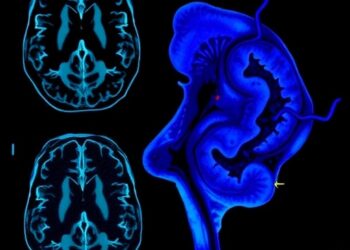

In a groundbreaking new study published in Translational Psychiatry, scientists have unveiled a compelling MRI-based signature that links accelerated brain ...